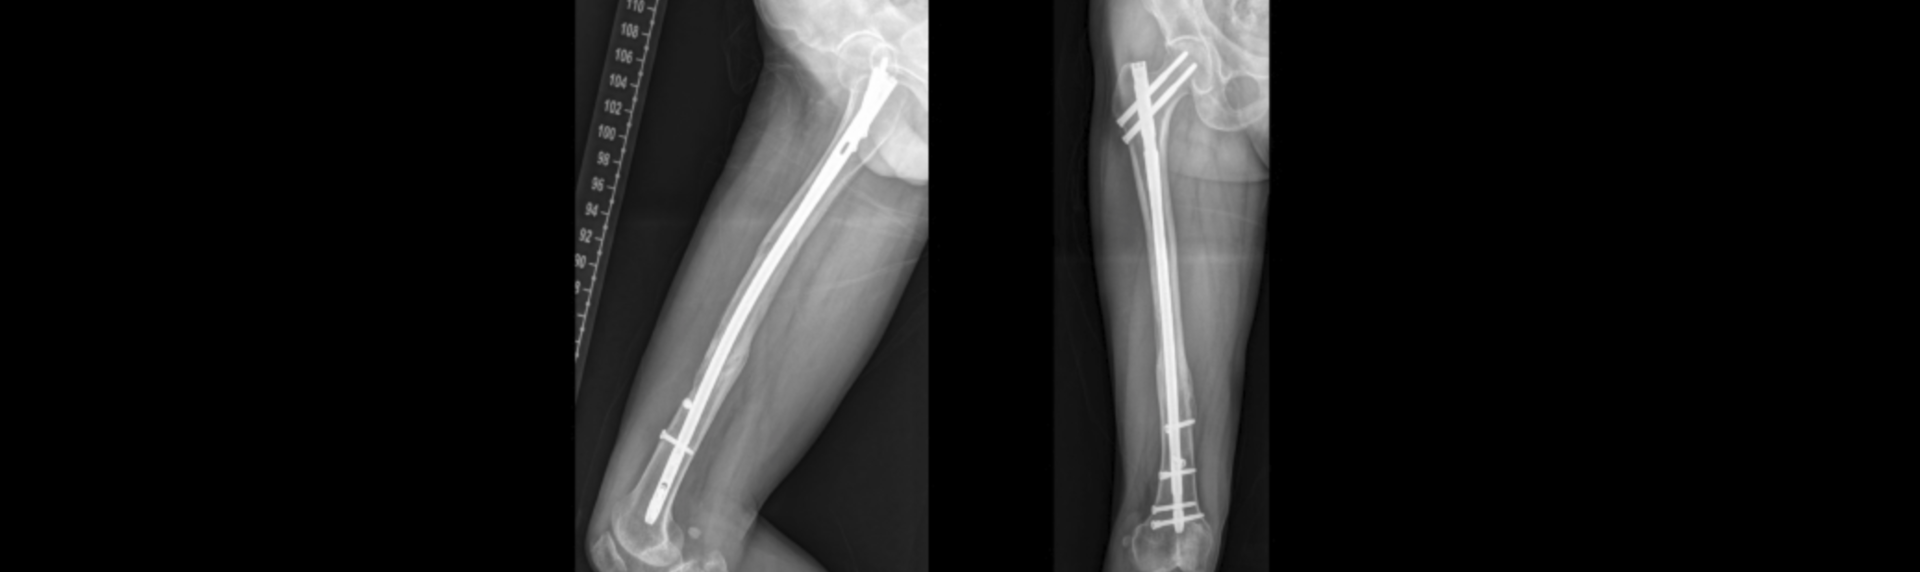

하지골절 치료방법

골절의 치료는 응급 치료, 본 치료, 재활 치료의 절차로 진행됩니다.

응급 치료는 부목 고정으로 추가적인 연부 조직 손상을 예방하고, 통증을 경감시키며, 환자의 엑스레이 검사를 용이하게 하는 목적으로 시행됩니다.

골절의 본 치료는 환자의 전신 상태가 안정된 후에 시행되며 손상 정도, 부위 및 합병증의 유무에 따라 세부적 치료 방법을 선택합니다.

※ 수술 및 시술 시 매우 드물게 출혈이나 감염, 혈전 등이 있을 수 있습니다.